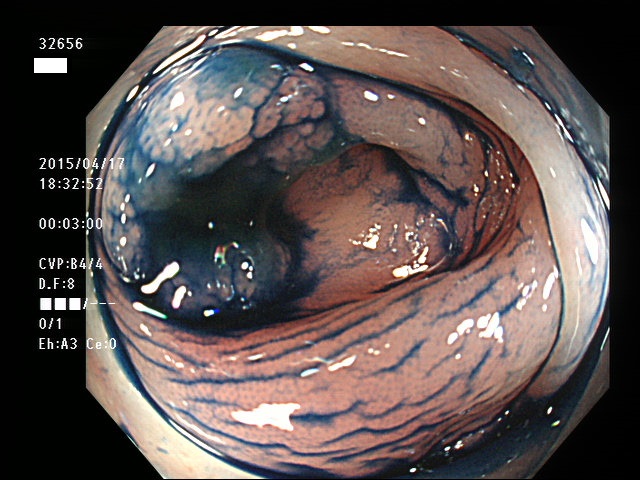

上記100名より抽出した平坦・陥凹型腺腫(=癌化の危険が高いが見落としやすい病変)の内視鏡写真